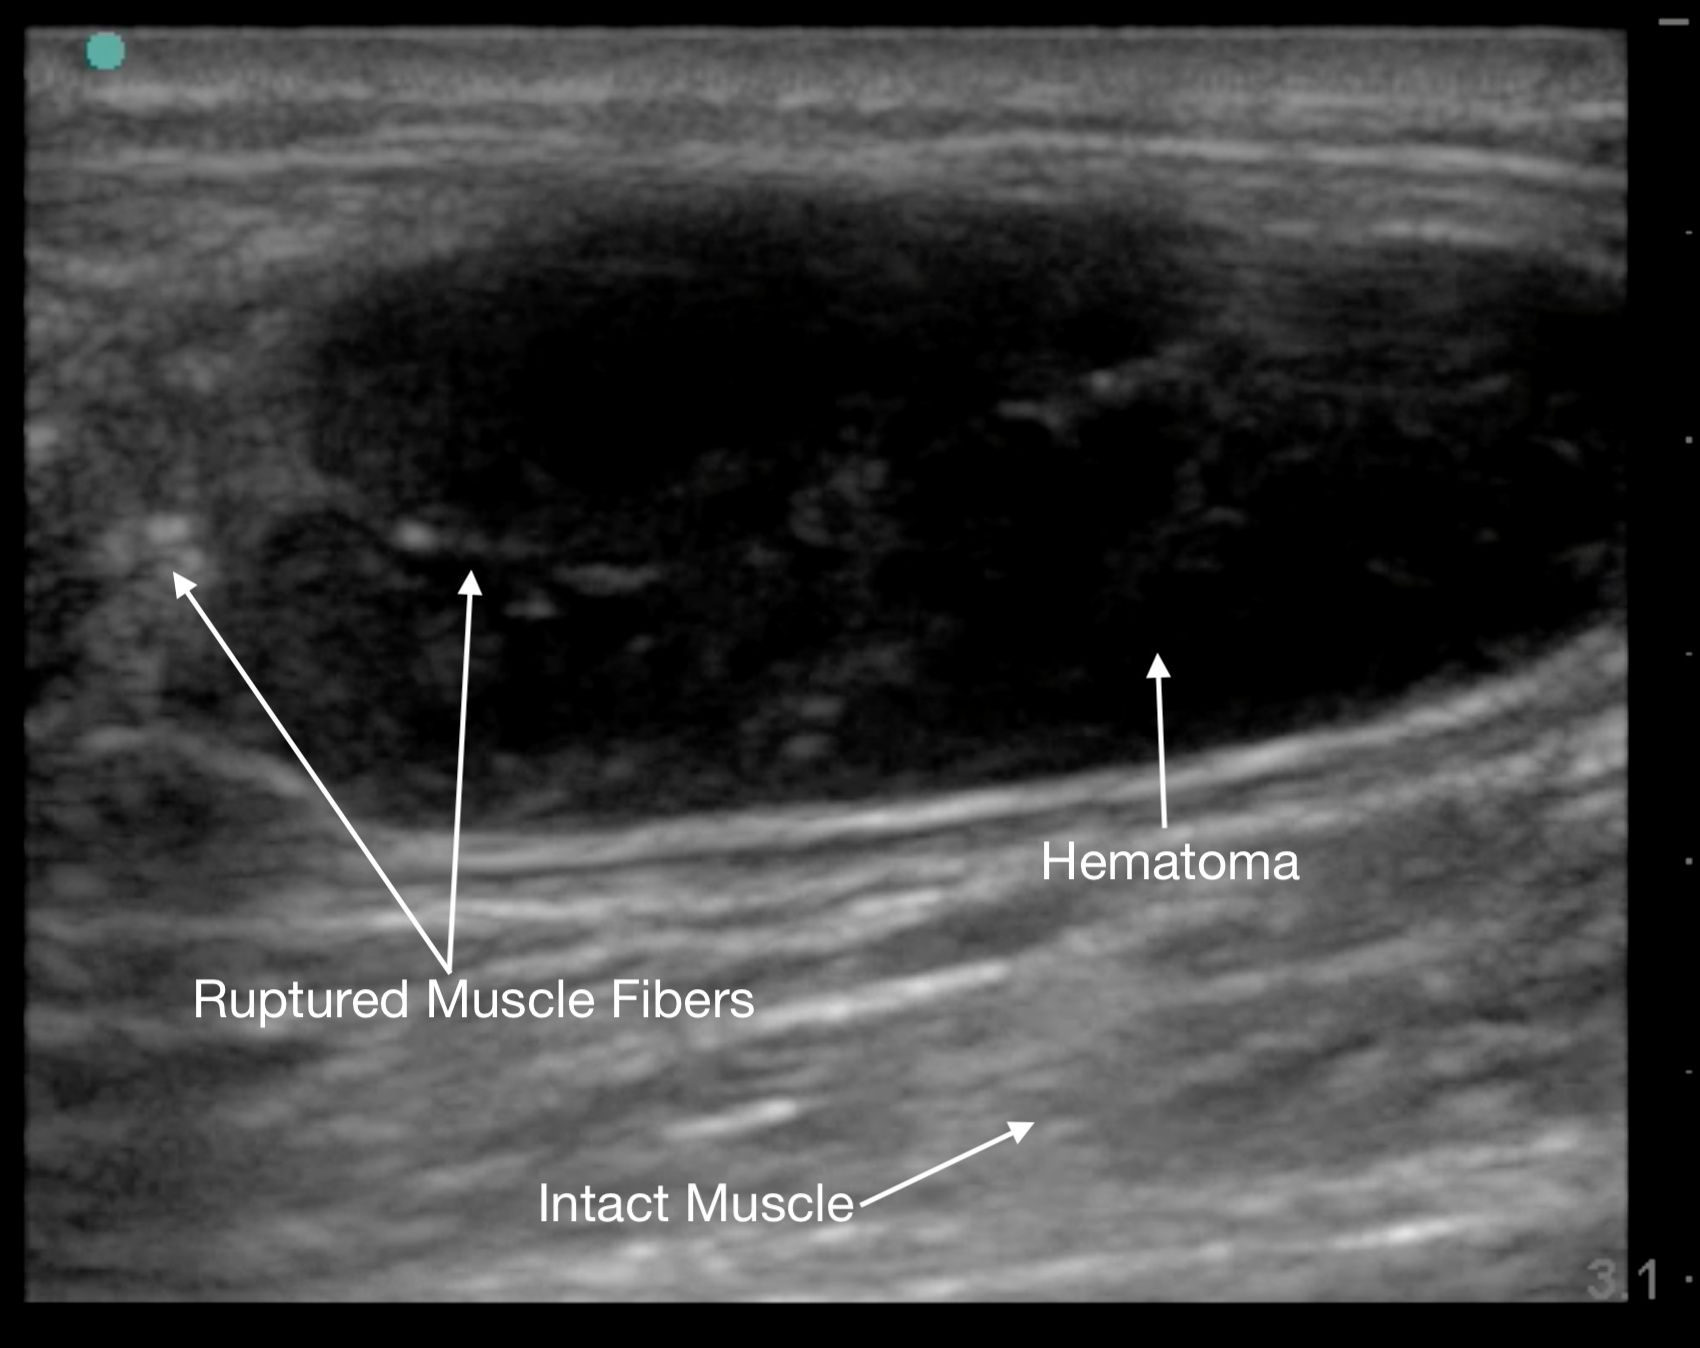

Tendon ruptures appear as areas of hypoechogenicity from edema/hematoma, and adjacent bunched up, retracted tendon fibers. For complete tears, the portion of the tendon near the injury will lose its rigid, straight appearance and instead appear irregular and have a large gap between the torn end and its insertion point. Partial tears are more subtle and will sometimes only have a small, cone-shaped hypoechoic focus. The key with tendon exams is to view them dynamically, having the patient flex and extend the injured joint (if possible).

Figure 13a.

A) Partial rupture of the patellar ligament at the distal insertion

Figure 13b.

a different patient with a complete rupture at the proximal insertion of the patellar tendon. The patella is on the left side of the image, and note the hematoma that wraps around the ruptured end of the tendo